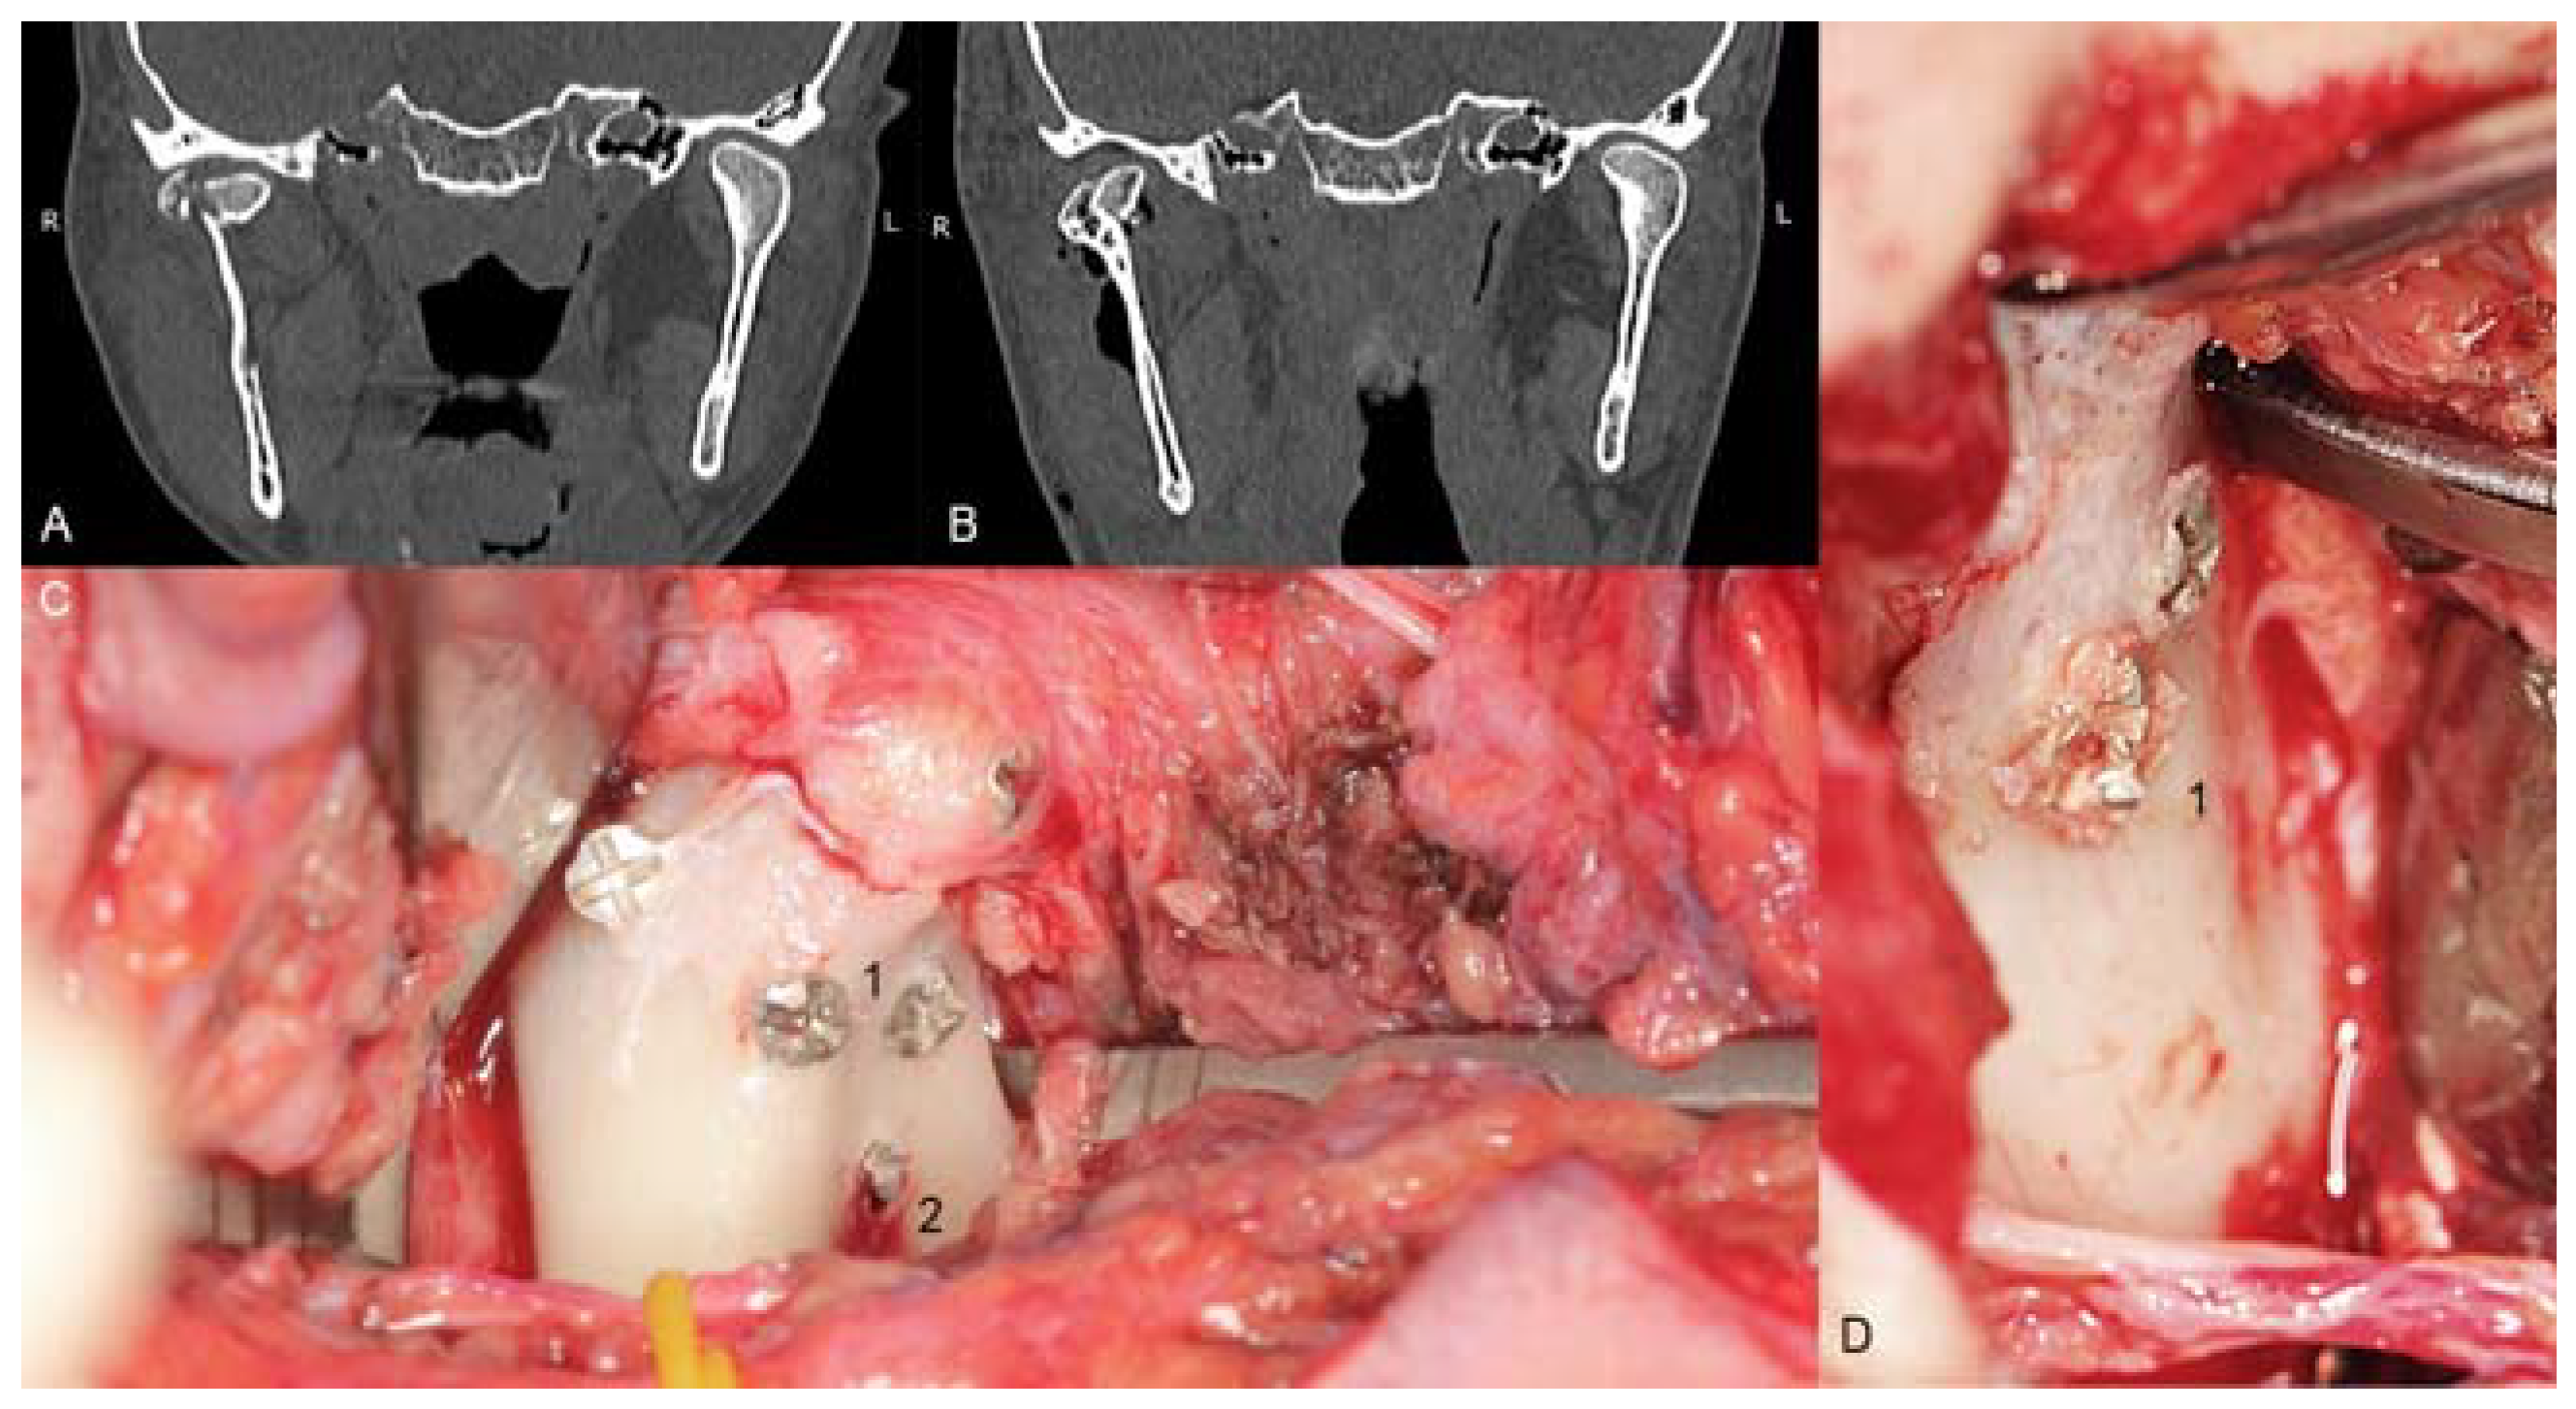

Unfortunately, the mechanical properties of medical magnesium alloys are poorer than those of titanium. It is possible to damage screws during fixation (Figure 1). Because these incidents can occur, the author of this study has proposed modifications in screw design to reinforce screws and achieve the dimensions given in Table 1. However, it is still important to compare new metal resorbable screws with standardized titanium and long-established polymers. Therefore, the aim of this work was to compare screws made specifically for mandibular head fixation from different materials.

Figure 1.

Examples of mechanical damage to the magnesium alloy screw. A and B—computed tomography images of the comminuted right head of the mandible (A) and images taken at the postoperative follow-up (B). Operative field of the same patients (C): screws inserted through the lateral pool and posterior head surface, and three screws inserted below the lateral pool. The dexter caput mandibulae fractura is shown in the next picture to the right (D): simple case of a Type B head fracture. Four of the 20 screws used became deformed. The decalibration of the slot for the screwdriver was observed (1) in all of them, once the core bend of 1.7 screws and the breaking of 1.7 screws was observed (2). Decalibration of the slot is not dangerous if the operator is aware of such circumstances, and these types of incidents can occur after the screw has been placed in the final position; however, bending and breaking of the screw compromises the integrity of osteosynthesis. All screws presented here are 1.7 mm system headless compressive screws (i.e., before the modification was tested in this study).